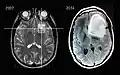

En début d'évolution, l'imagerie montre une tumeur isodense au scanner, d'où l'intérêt de l'IRM, plus sensible au dépistage de cette tumeur peu vascularisée. Lors de l'évolution, le scanner montre une tumeur hypodense, ne prenant généralement pas le produit de contraste. Il n'est pas retrouvé d'effet de masse puisque la tumeur est infiltrante.

Une biopsie peut être envisagée pour confirmer le diagnostic d'astrocytome, préciser le grade histologique.